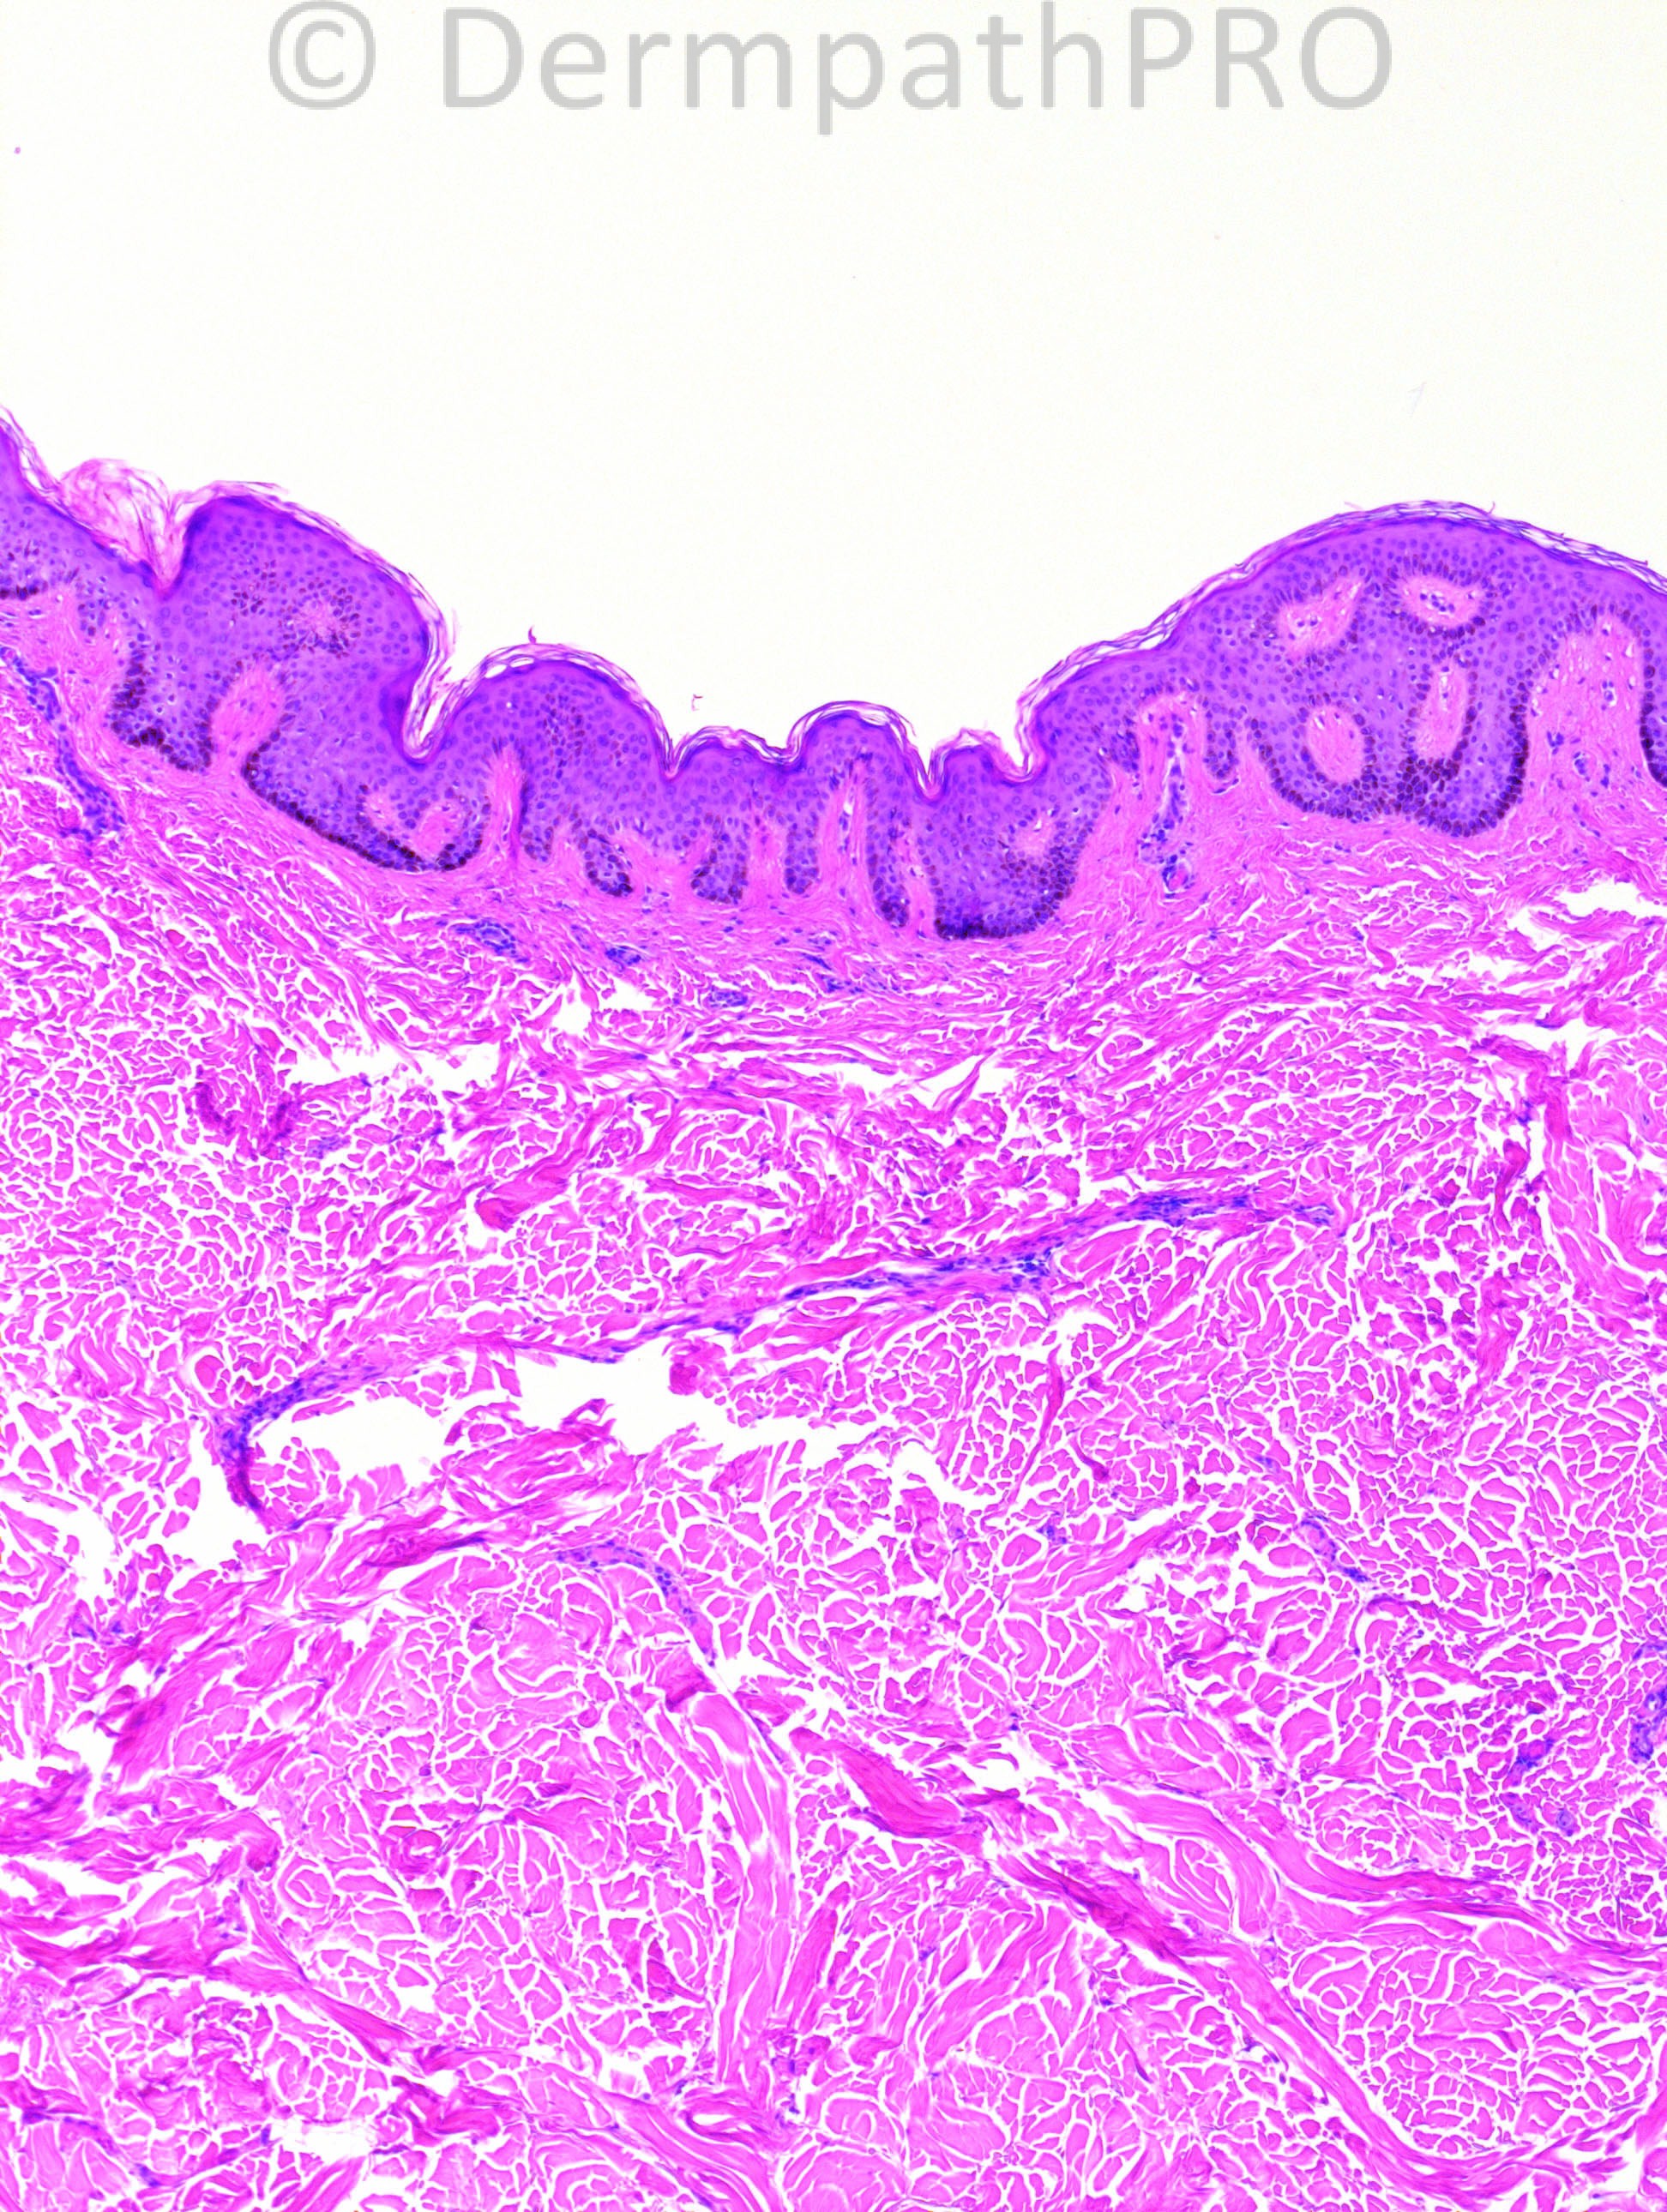

52 years-old female with left back lesion: a dimpled, soft plaque.

Case posted by Dr. Hafeez Diwan.